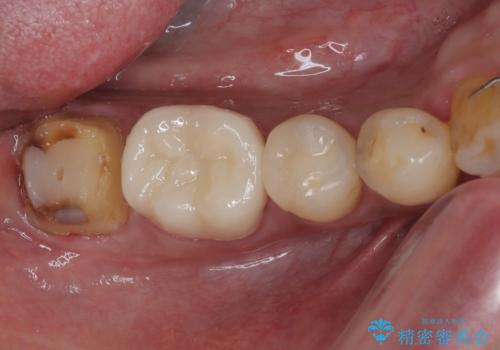

- 銀歯を外して虫歯治療をしたいとのことで来院された患者様です。右下の7番目の歯は銀歯の下に虫歯が広がっており根管治療の可能性もあることを説明したうえで治療を行いました。

左下の5番目の歯はセラミックインレー修復で治療を行うことにしました。

左下の7番目の歯は仮歯に置き換えた後自発痛、咬合痛の所見を認めたので、当院院長である藤巻先生に担当してもらっています。